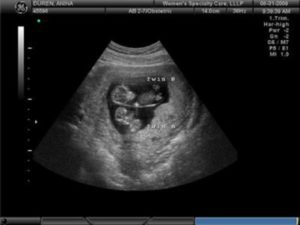

Узи двойни при беременности: фото на ранних сроках в 5-6 недель и позже

Определение двойняшек и близнецов осуществляется таким продуктивным методом исследования, как УЗИ. Этот вид обследования обеспечивает информацией о месте расположения ребенка, имеется ли многоплодная беременность и др.

Как правило, двое эмбрионов четко определяют на УЗИ с самых ранних недель — 5-7. Позже врач способен это определить и без применения ультразвуковой диагностики. Двойняшек можно выявить по такому признаку, как увеличенный размер матки, уже с ранних сроков, а медицинская диагностика с применением ультразвука покажет двух детей только на 1 скрининге — в 10-14 недель.

Двойняшки покажутся на УЗИ уже с 5 недели

В таком случае УЗИ эмбрионов покажет наличие двойни уже на 5 неделе, особенно с применением высокочувствительных датчиков 3д-сканирования. Осмотр дает возможность определить двойняшек только на сроке 9-11 недель.

Следовательно, наличие двойняшек в утробе выявляется посредством ультразвука уже через месяц после зачатия, на снимке они выглядят как 2 образования темного цвета внутри полости матки (см. фото УЗИ-обследования двойни ниже).

Увидеть двойню на УЗИ при беременности можно уже через месяц после зачатия. В этом случае специалист отметит на экране монитора два пятна черного цвета, которые хорошо просматриваются ультразвуком